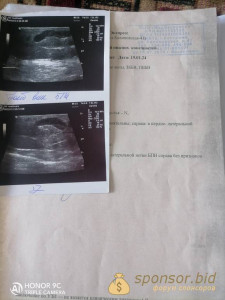

Здравствуйте всем,меня зовут Кристина, моей подруге требуется помощь,я все что чем смогла помогла, люди добрые крик души, помогите пожалуйста, не кому помоч ей 36 лет, родных родственников нет детдомовская,детство у нее не простое было, живет в двоем сыном, для которого хочет жить, нашли тромбы в венах, сколько случаев эти тромбы разрываються, таблетки мази не помогают, квот бесплатных нет, да и живем в деревне где помощи мало, операция 40000 тысяч р. На собирали только 20000, давайте поможем кто сколько может по 10, 20, 30,40,50 рублей 2200 7704 4899 4527 карта почта банк.

Все выписки документы есть можем скинуть. Позвонить можите +79960490105 помогите пожалуйста не проходите мимо. Люди добрые дай бог всем крепкого здоровья кто поможет.